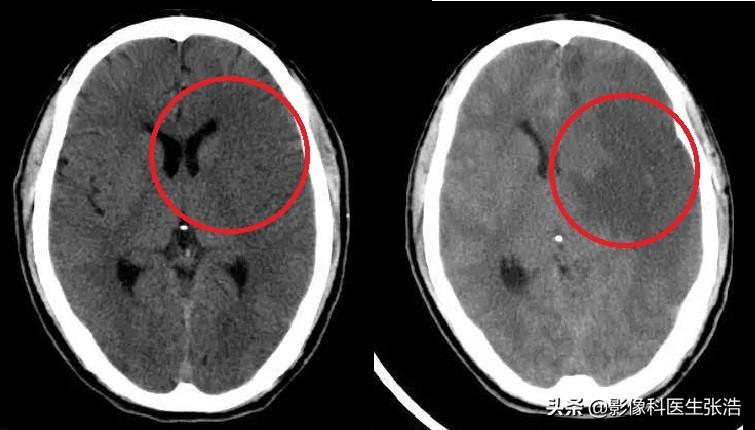

腦梗的診斷主要依據(jù)患者的病史、體格檢查和影像學(xué)檢查,醫(yī)生會(huì)根據(jù)患者的癥狀、體征以及可能的病因進(jìn)行初步判斷,并結(jié)合頭顱CT、MRI等影像學(xué)檢查來確診。